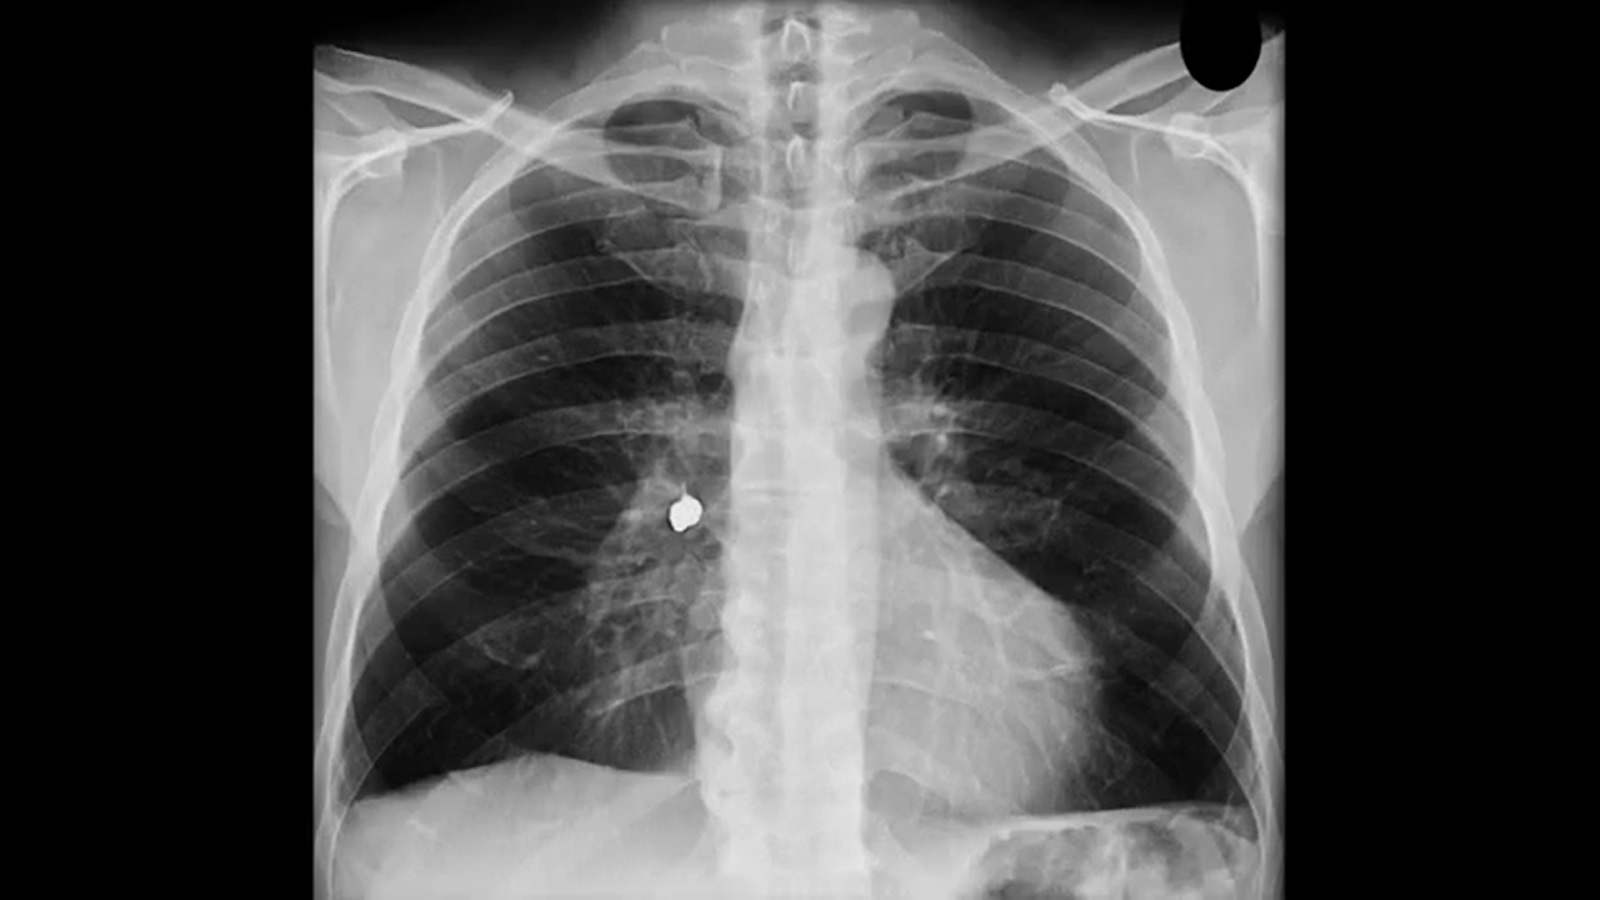

“O grande risco é quando o corpo estranho fica alojado no esôfago, local com mais sintomas e risco”, explica Giovana Tuccille Comes Brambilla, cirurgiã pediátrica do HCFMB. Segundo a especialista, o raio-x simples é o exame capaz de identificar a presença de um corpo estranho.